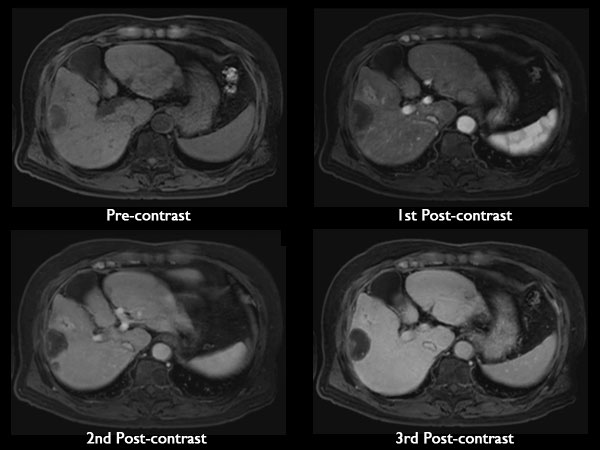

Axial dynamic mDIXON (Water Only)